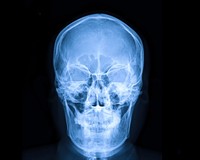

Рентгерографія (рентген) — це один із методів, що ґрунтується на рентгенодіагностиці, метою якого є отримання зображення об'єкта на спеціальній плівці.

Найчастіше рентгенографію роблять, якщо є підозра на перелом кісток.

Суть дослідження в тому, що рентгенівські промені проходять через тканити тіла. Кістки на плівці матимуть білий колір. Якщо кістка пошкоджена (тріщина чи перелом) на знімку буде помітно "розрив" у білому забарвлені кістки.